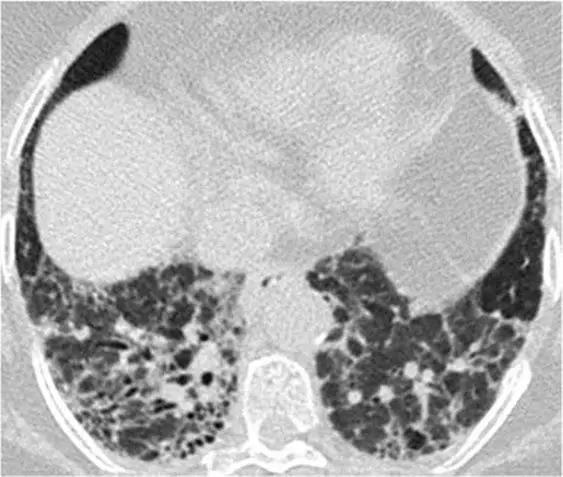

3、磨玻璃影模式

HRCT上的磨玻璃样改变被定义为不透明的薄雾影增加,并保留了支气管和血管标记。经典疾病:亚急性过敏性肺炎(HP),其特征是磨玻璃样混浊的对称斑片或弥散性双侧区域,伴有边界义不清的小叶中心型结节。有助于将亚急性HP与其他相似疾病分开的特征是,在吸气图像和气管呼气图像上,小叶区域的衰减和多血管影。磨玻璃样的最常见的鉴别疾病是呼吸性毛细支气管炎相关的间质性肺病(RB-ILD)、脱屑性间质性肺炎(DIP)和肺囊虫性肺炎。

*亚急性过敏性肺炎。 HRCT显示“磨玻璃样”改变,有少量小叶结构,没有纤维化改变

RB-ILD可表现为中度到广泛性的双侧磨玻璃影,边界不清的小叶中心型结节,支气管壁增厚。有时,在肺基部可能会出现轻微的网状结构。区分RBILD和亚急性HP的线索是RB-ILD存在上叶轻度肺气肿,HP吸烟者存在吸烟习惯的改变。

*RB-ILD 上叶水平的HRCT显示弥散的“毛玻璃样”,小叶透亮区代表伴随的小叶肺气肿。